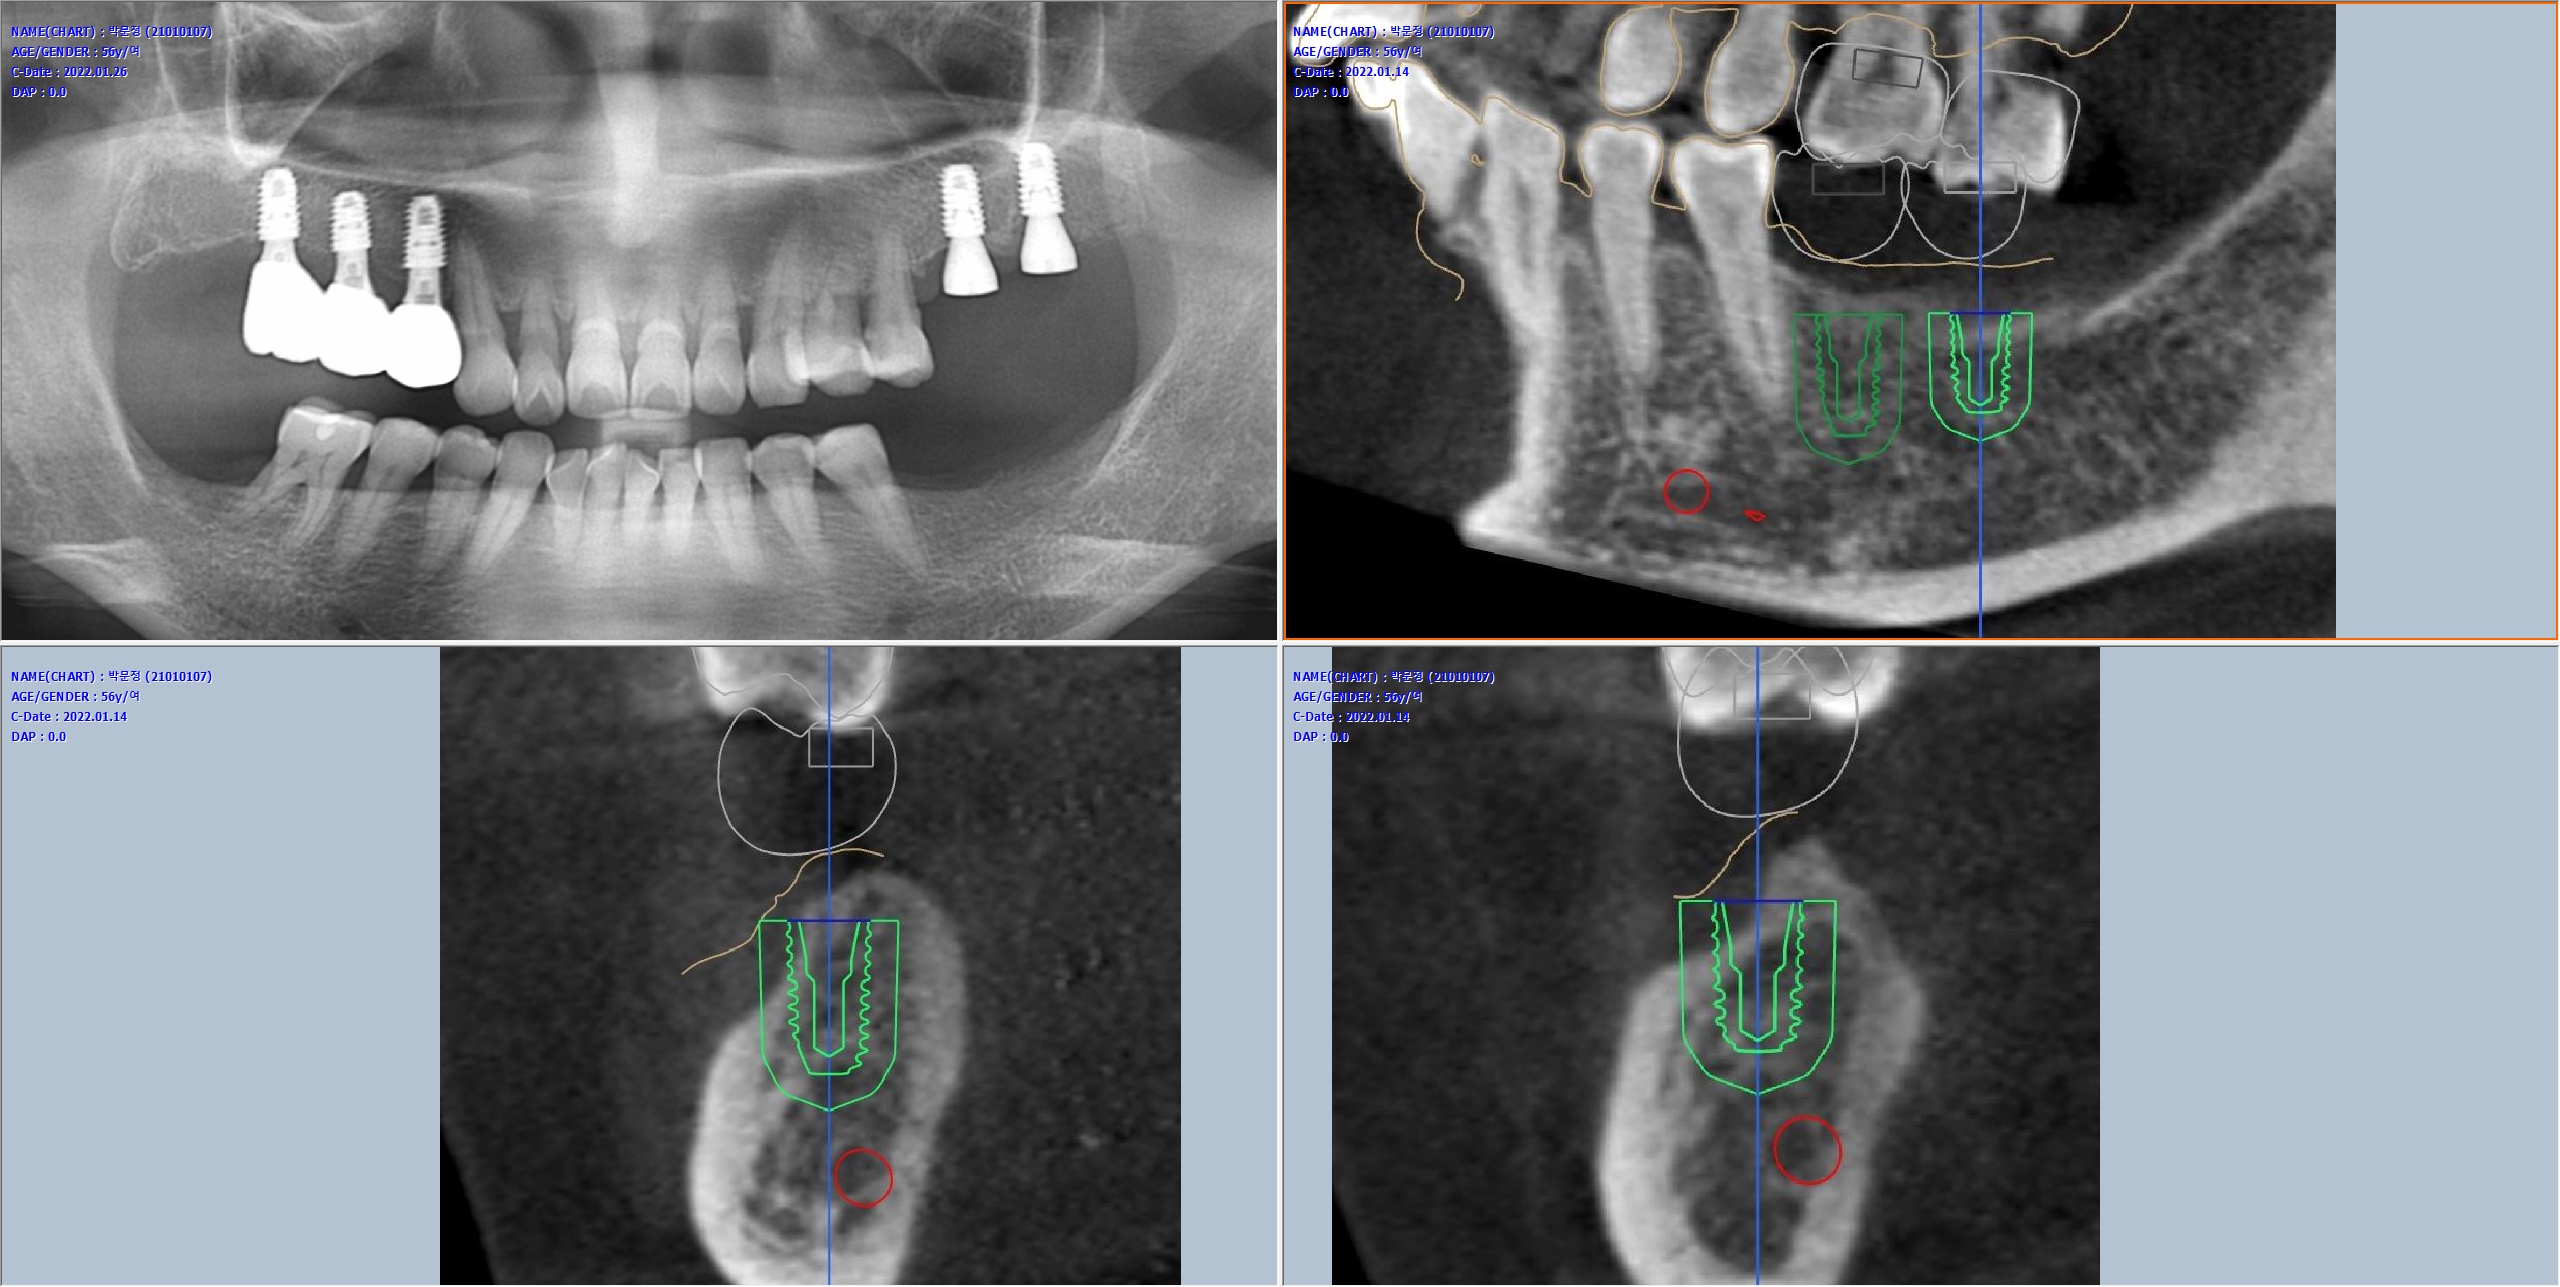

모든 임플란트는 네비게이션을 이용하여 식립했습니다.

사진: 네비게이션 임플란트 계획